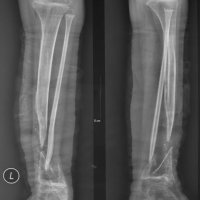

Titanium Elastic Nailing (TEN) is intended for fixation of diaphyseal fractures of long bones where the medullary canal is narrow or flexibility of the implant is paramount. The biomechanical principal of the Titanium elastic nailing is based on the symmetrical bracing action of two elastic nails inserted into the metaphysis, each of which bears against the inner bone at three points. The complication rates associated with Titanium elastic nailing have been reported to be minimal.

Congenital pseudarthrosis of the tibia (CPT) refers to nonunion of a tibial fracture that develops spontaneously or after a minor trauma. It is a rare pathology, occurring in only 1 out of 250,000 births. The cause of CPT is currently unknown; however, there is a strong association with neurofibromatosis in 50% of cases and an association with fibrous dysplasia in 10% of cases. The pseudarthrosis usually develops within the first two years of life; but may be undetected up to the age of 12 years. Bilateral occurence is rare; the fibula is affected in one third of the patients.

Congenital tibial pseudoarthrosis is characterized by segmental osseous weakness, resulting in anterolateral angulation of the bone. Reports indicate the pathologic processes of CPT are linked to the periosteum, which forms the outer layer of bones and is crucial for regrowth following a fracture. Patients with CPT have a thick scar layer surrounding their bones rather than the periosteum. For this reason, once a fracture has occurred it will not heal spontaneously.

Classification systems describing prognostic radiographic characteristics, natural history, onset, mobility, therapeutic guidelines, and variables influencing the outcomes have been proposed by many different authors. Three classifications of CPT are commonly used. The Andersen classification differentiates the morphology of pseudoarthrosis as dysplastic, cystic, or sclerotic types, in addition to a clubfoot type that arises because of accompanying abnormalities. Crawford described four types of CPT, all types have in common an anterolateral bowing of the affected tibia. The classification of pseudoarthrosis by Boyd consists of six types and includes a type V, which is characterized by a complementary dysplastic fibula and a type VI, in which an intraosseous neurofibroma or schwannoma is evident.

While many classification systems exists, the most important criterion is the status of the tibia (fractured versus intact). Treatment is mainly surgical, with bracing used to supplement surgical procedures.